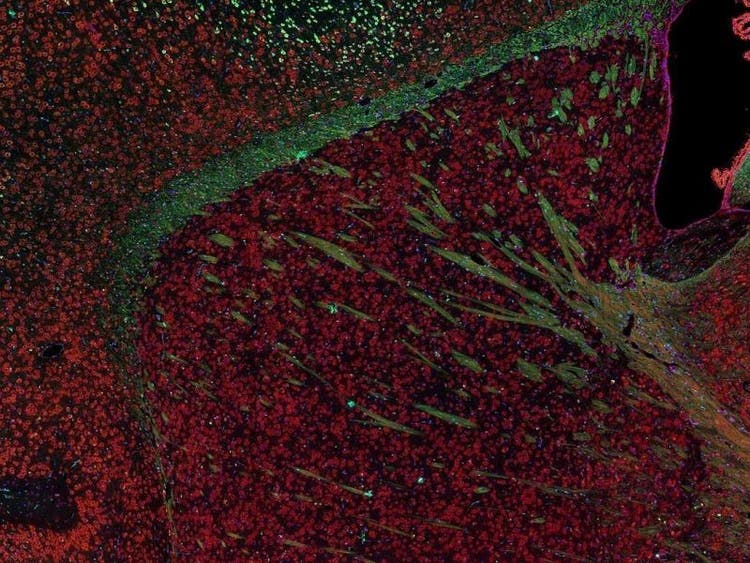

Fluorescence imaging of a mouse brain

While each of these images looks distinct up close, they all come together to form one view of a mouse brain captured with fluorescence imaging.